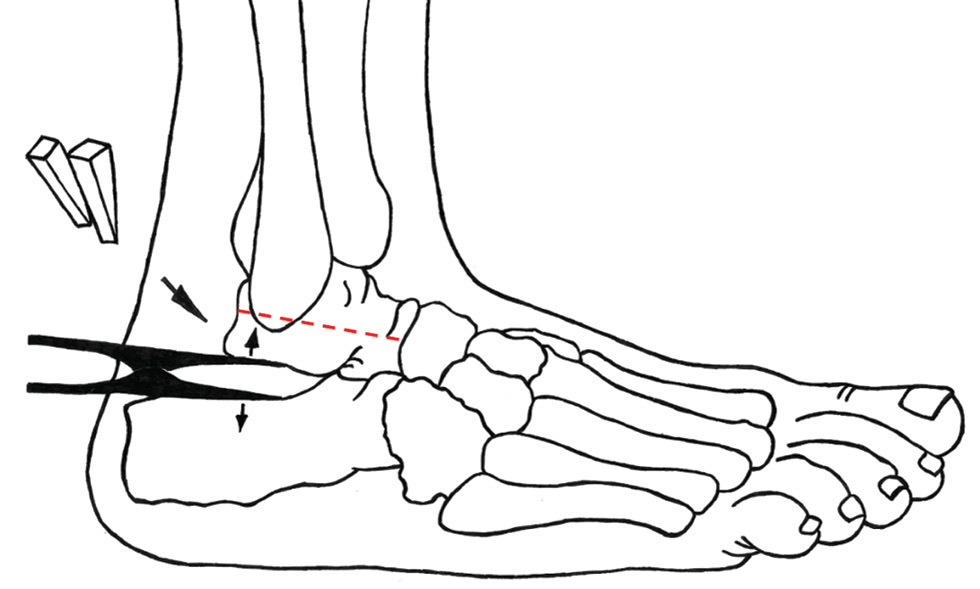

После проведения анестезиологического пособия (спинальная анестезия) проводился задне-наружный, продольный или слегка дугообразный (дистально) доступ между наружной лодыжкой и ахилловым сухожилием до подошвенной поверхности стопы (при отсутствии предыдущего послеоперационного рубца) (рис. 1).

Рис. 1. I-образный доступ по Gallie. Пунктиром показано горизонтальное положение таранной кости.

Fig. 1. I-shaped approach according to Gallie. The dotted line indicates the horizontal position of the talus.